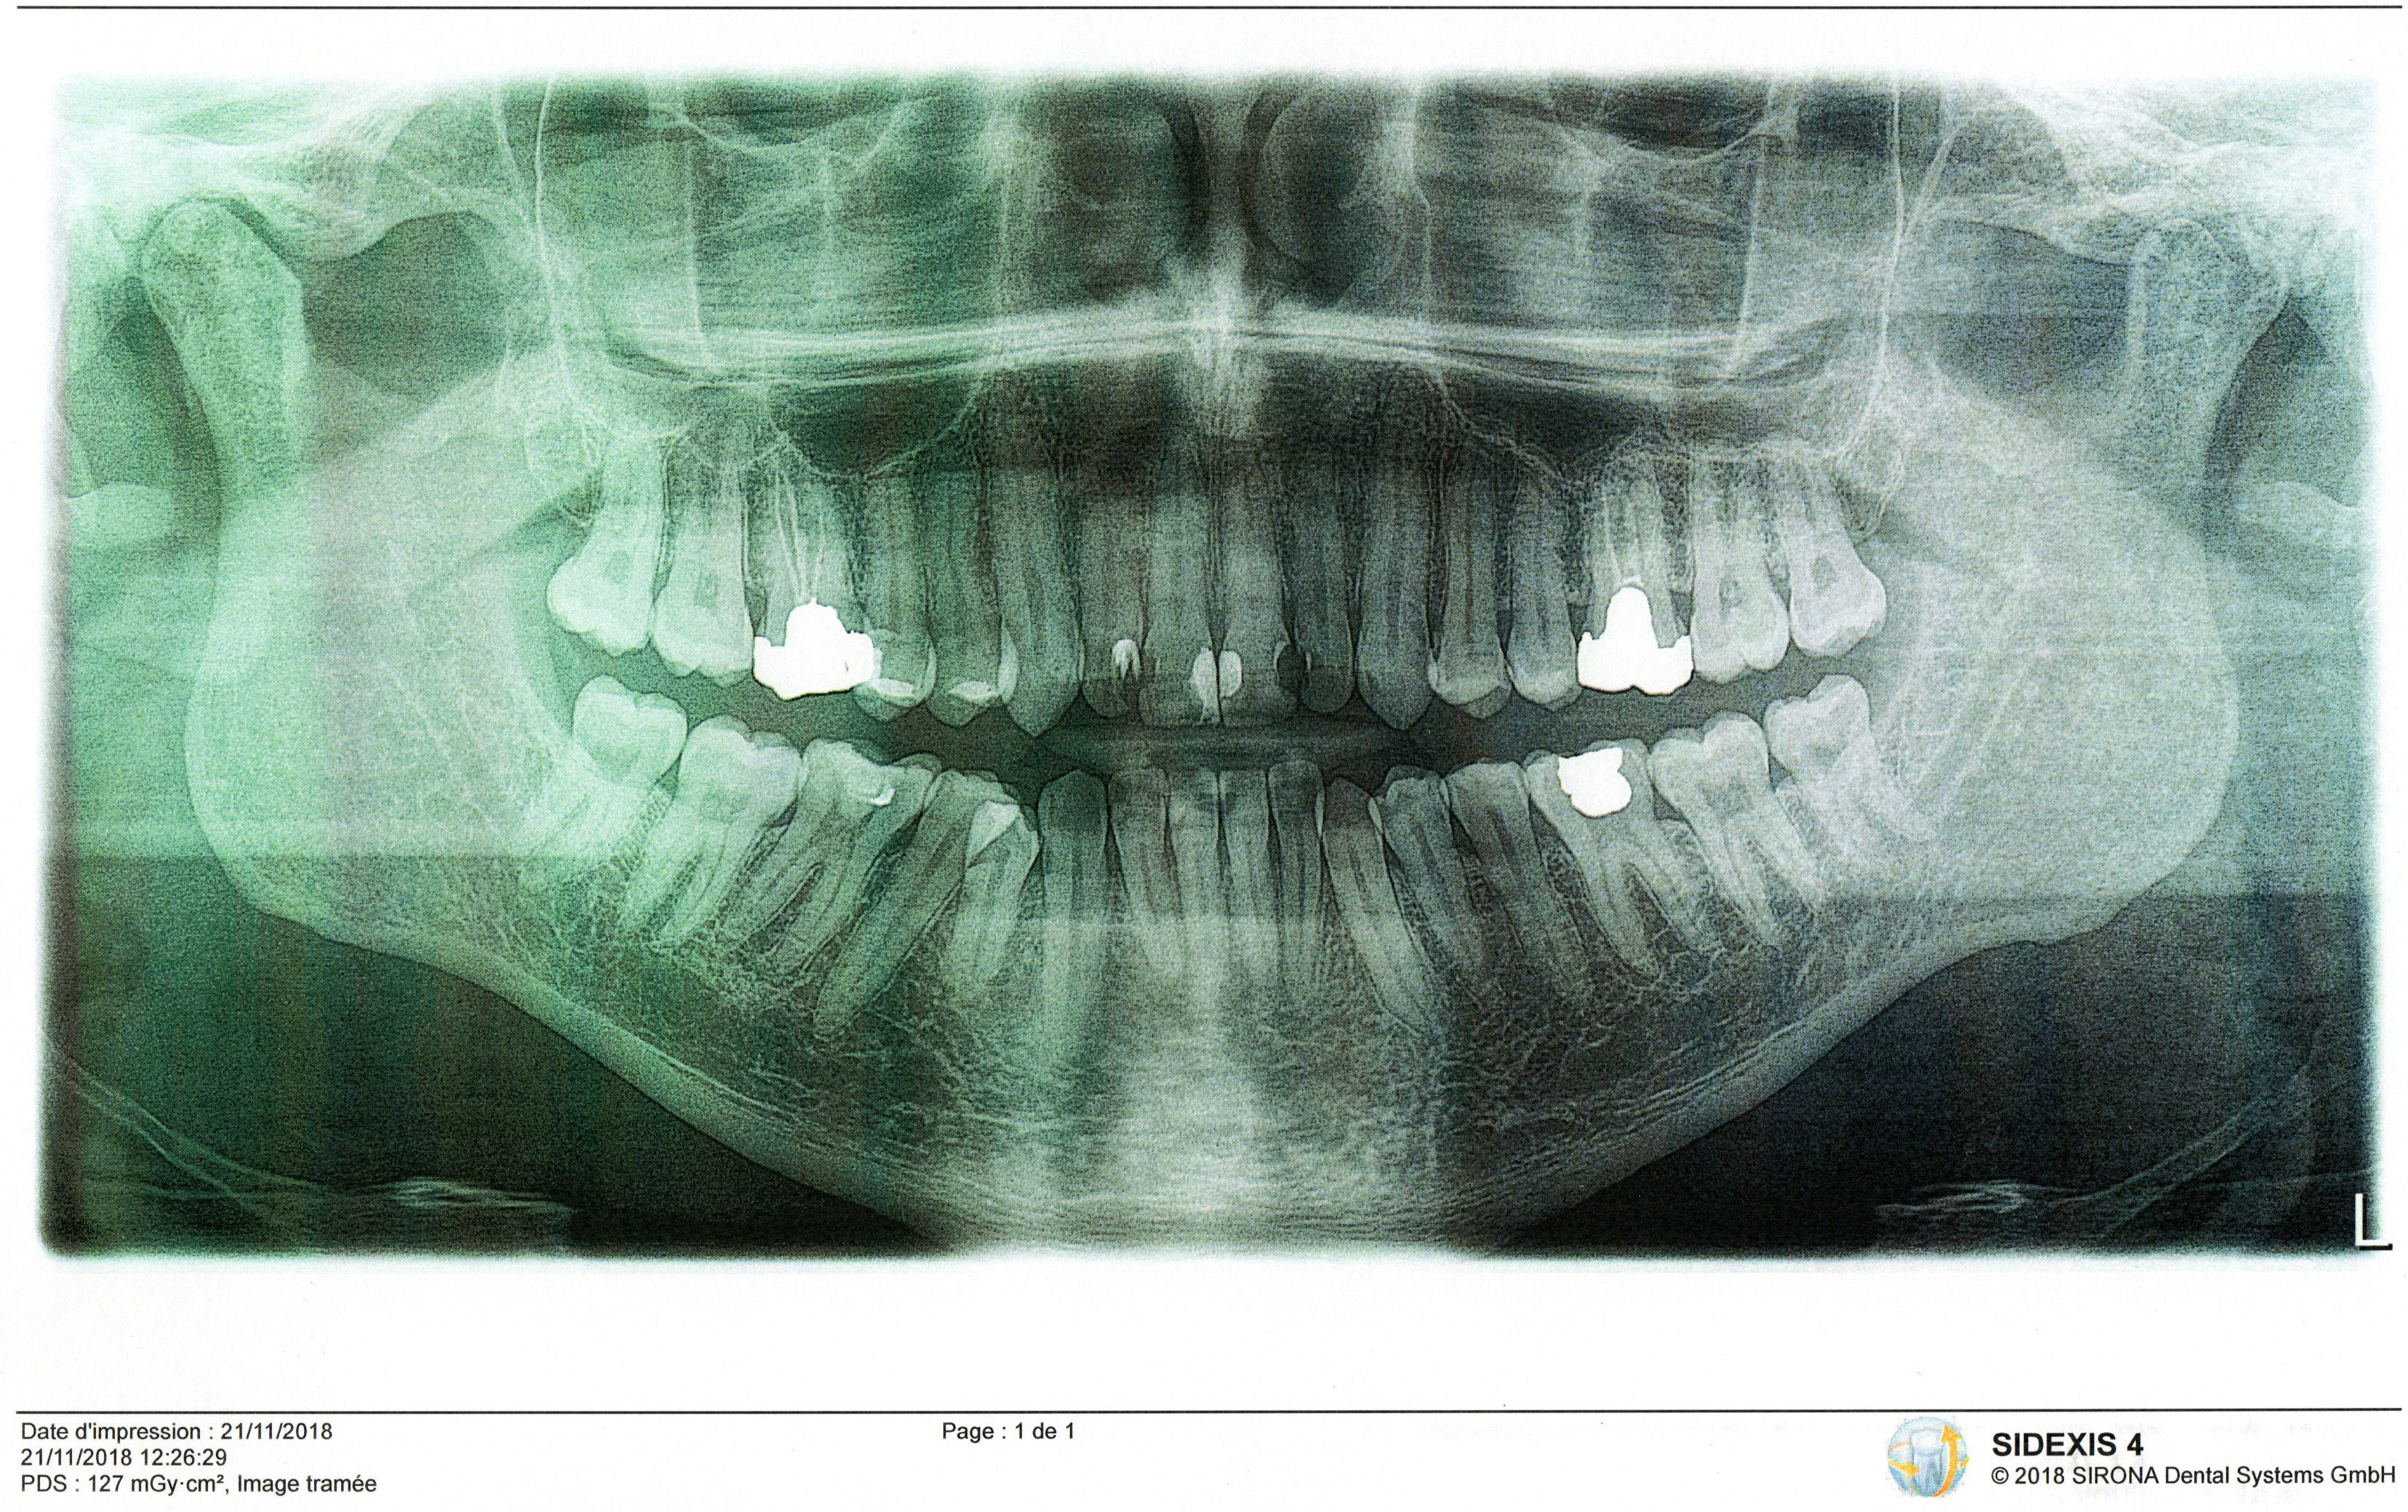

Serguei Опубликовано 20 августа, 2019 Поделиться Опубликовано 20 августа, 2019 Здравствуйте! У меня 3й и 14й моляры верхней челюсти, около пяти лет назад удалены нервы и поставлены металлические ртутные пломбы, сами эти два зуба со временем потемнели.Вокруг этих зубов началось убывание десны и костной ткани, к тому же это понемножку распространяется на окружающие зубы (премоляры и моляры 2 и 15). Вопрос:Что может помочь остановить убывание кости и десны в данной ситуации? Поможет ли замена металлических пломб на коронки? Что является причиной пародонтоза вокруг этих зубов?1. Удаление нервов ?2. Металлические пломбы? 3. и то и другое. 4. или вышеперечисленные факторы не всегда приводят к парадонтозу. Может быть стоит искать причину в общем состоянии организма? Щитовидка? Проходил проверку в специализированной клинике, пародонтит не подтвержден, значит остается пародонтоз. Рентген снимок прилагается. Спасибо.Сергей. 1 Ссылка на комментарий

Serguei Опубликовано 21 августа, 2019 Автор Поделиться Опубликовано 21 августа, 2019 Рентгеновский снимок: Ссылка на комментарий

red_butler Опубликовано 21 августа, 2019 Поделиться Опубликовано 21 августа, 2019 по снимку пародонтит легкой степени Что может помочь остановить убывание кости и десны в данной ситуации? полноценная индивидуальная гигиена Что является причиной пародонтоза вокруг этих зубов? бактериальный налет Ссылка на комментарий

red_butler Опубликовано 21 августа, 2019 Поделиться Опубликовано 21 августа, 2019 Почему не пародонтоз?Как по снимку можно отличить?В клинике проверили бактериальную фауну и сказали что с этой стороны проблем нету. Ну во первых потому что в настоящее время такого диагноза нетНа снимке я вижу резорбцию костных пиков, это во вторых. Ссылка на комментарий

dentikl Опубликовано 21 августа, 2019 Поделиться Опубликовано 21 августа, 2019 по снимку-парадонтит в чистом виде. Ссылка на комментарий